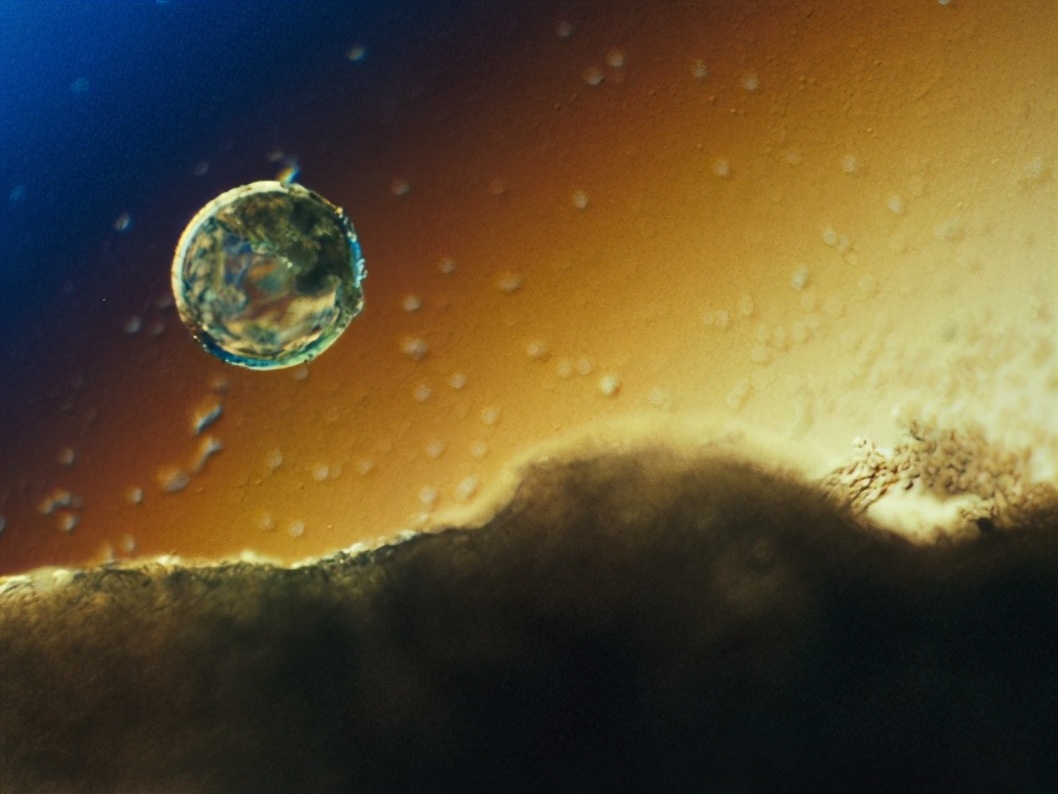

每个人都是从囊胚发育而来。卵子在受精后的几天内会发育成囊胚——直径仅约头发丝粗细(约120微米)的球形结构,由上胚层、原始内胚层以及滋养层三类细胞组成。其中上胚层细胞会发育成成体的各种组织,而原始内胚层细胞和滋养层细胞则发育成胎盘等胚胎外组织连接母体并为胚胎继续发育提供支持。

他们均发现人囊胚样结构在培养6-8天后出现,其大小、形状以及细胞总数与天然囊胚相似。这些细胞结构都含有一个腔体和类似内细胞团的细胞簇。进一步全基因组表达分析表明,它们的细胞类型与着床前的人类囊胚中细胞具有相同的分子标记,滋养层、外胚层、和内胚层三个细胞谱系的空间组织与着床前的人类囊胚相似。